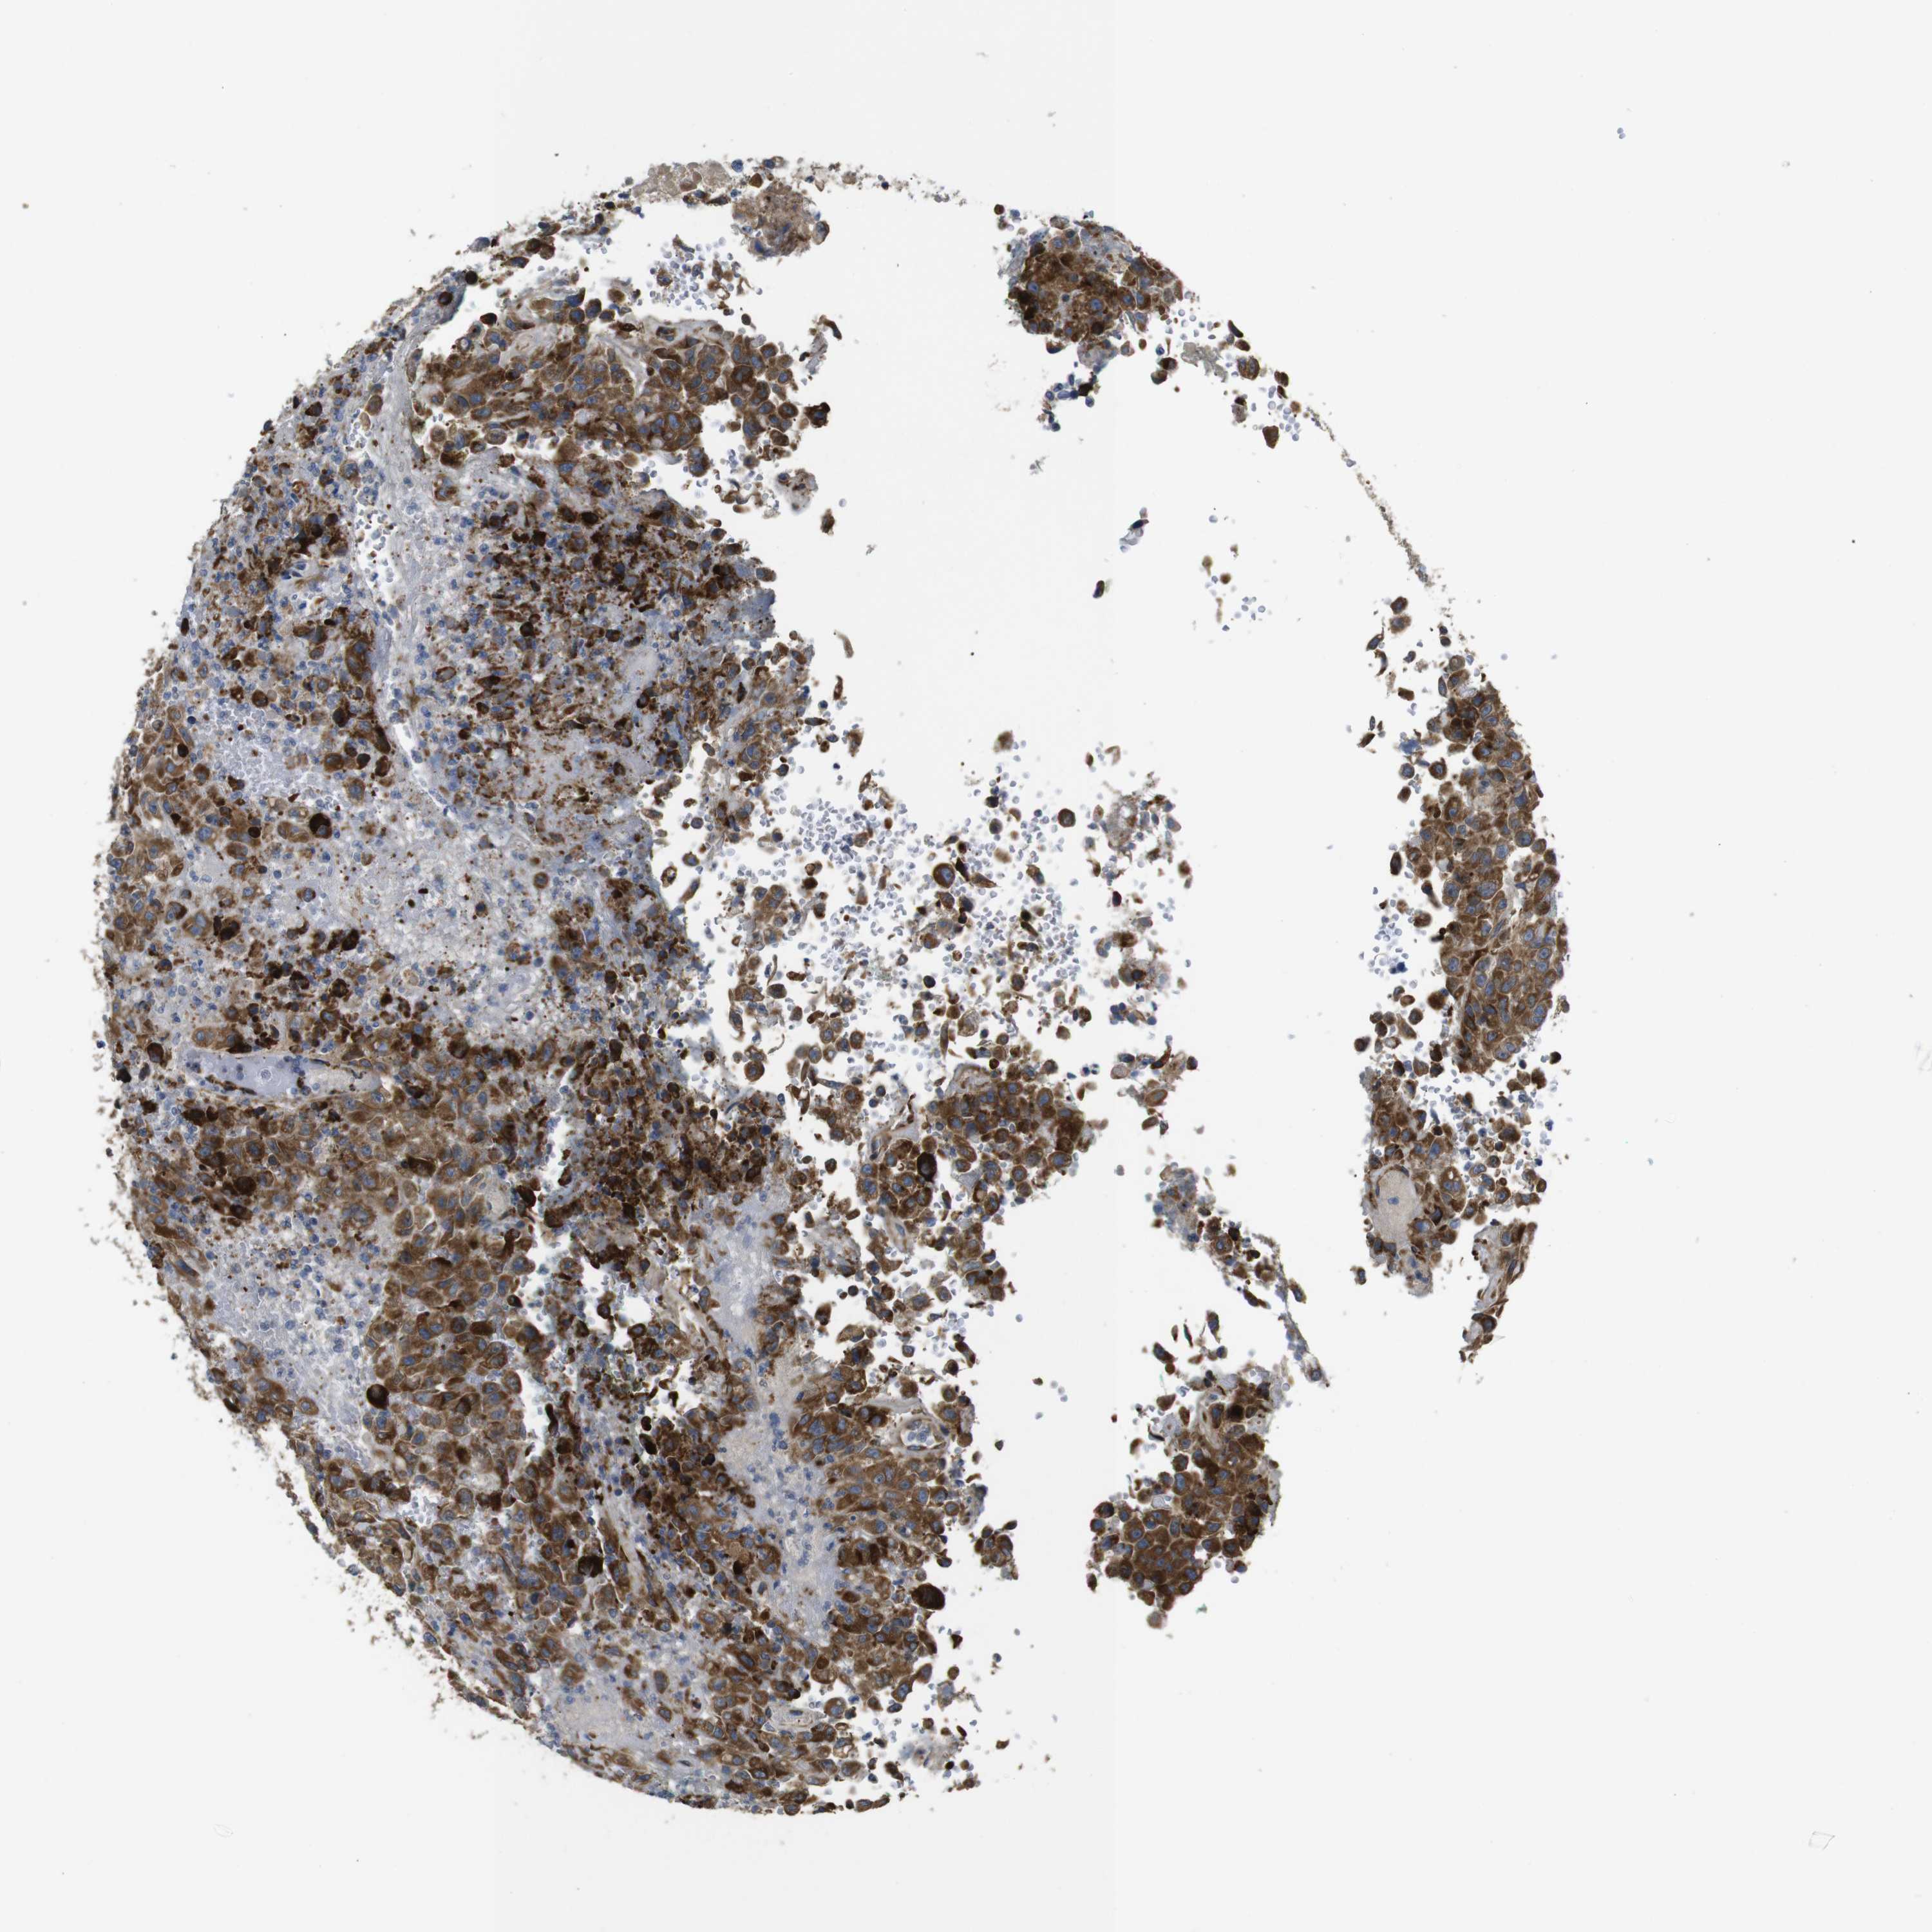

UROTHELIAL CANCER - Protein expressioni

A mouse-over function shows sample information and annotation data. Click on an image to view it in a full screen mode. Samples can be filtered based on level of antibody staining by selecting one or several of the following categories: high, medium, low and not detected. The assay and annotation is described here.

Note that samples used for immunohistochemistry by the Human Protein Atlas do not correspond to samples in the TCGA dataset.

Antibody stainingi

Antibody staining in the annotated cell types in the current human tissue is reported as not detected, low, medium, or high, based on conventional immunohistochemistry profiling in selected tissues. This score is based on the combination of the staining intensity and fraction of stained cells.

Each image is clickable and will lead to virtual microscopy that enables deeper exploration of all samples and also displays staining intensity scores, fraction scores and subcellular localization as well as patient and tissue information for each sample.

Antibody HPA003332

Staining

High

Medium

Low

Not detected

Intensity

Strong

Moderate

Weak

Negative

Quantity

>75%

75%-25%

<25%

None

Location

Nuclear

Cytoplasmic/membranous

Cytoplasmic/membranous,nuclear

Urothelial carcinoma, Low grade

Urothelial carcinoma, High grade